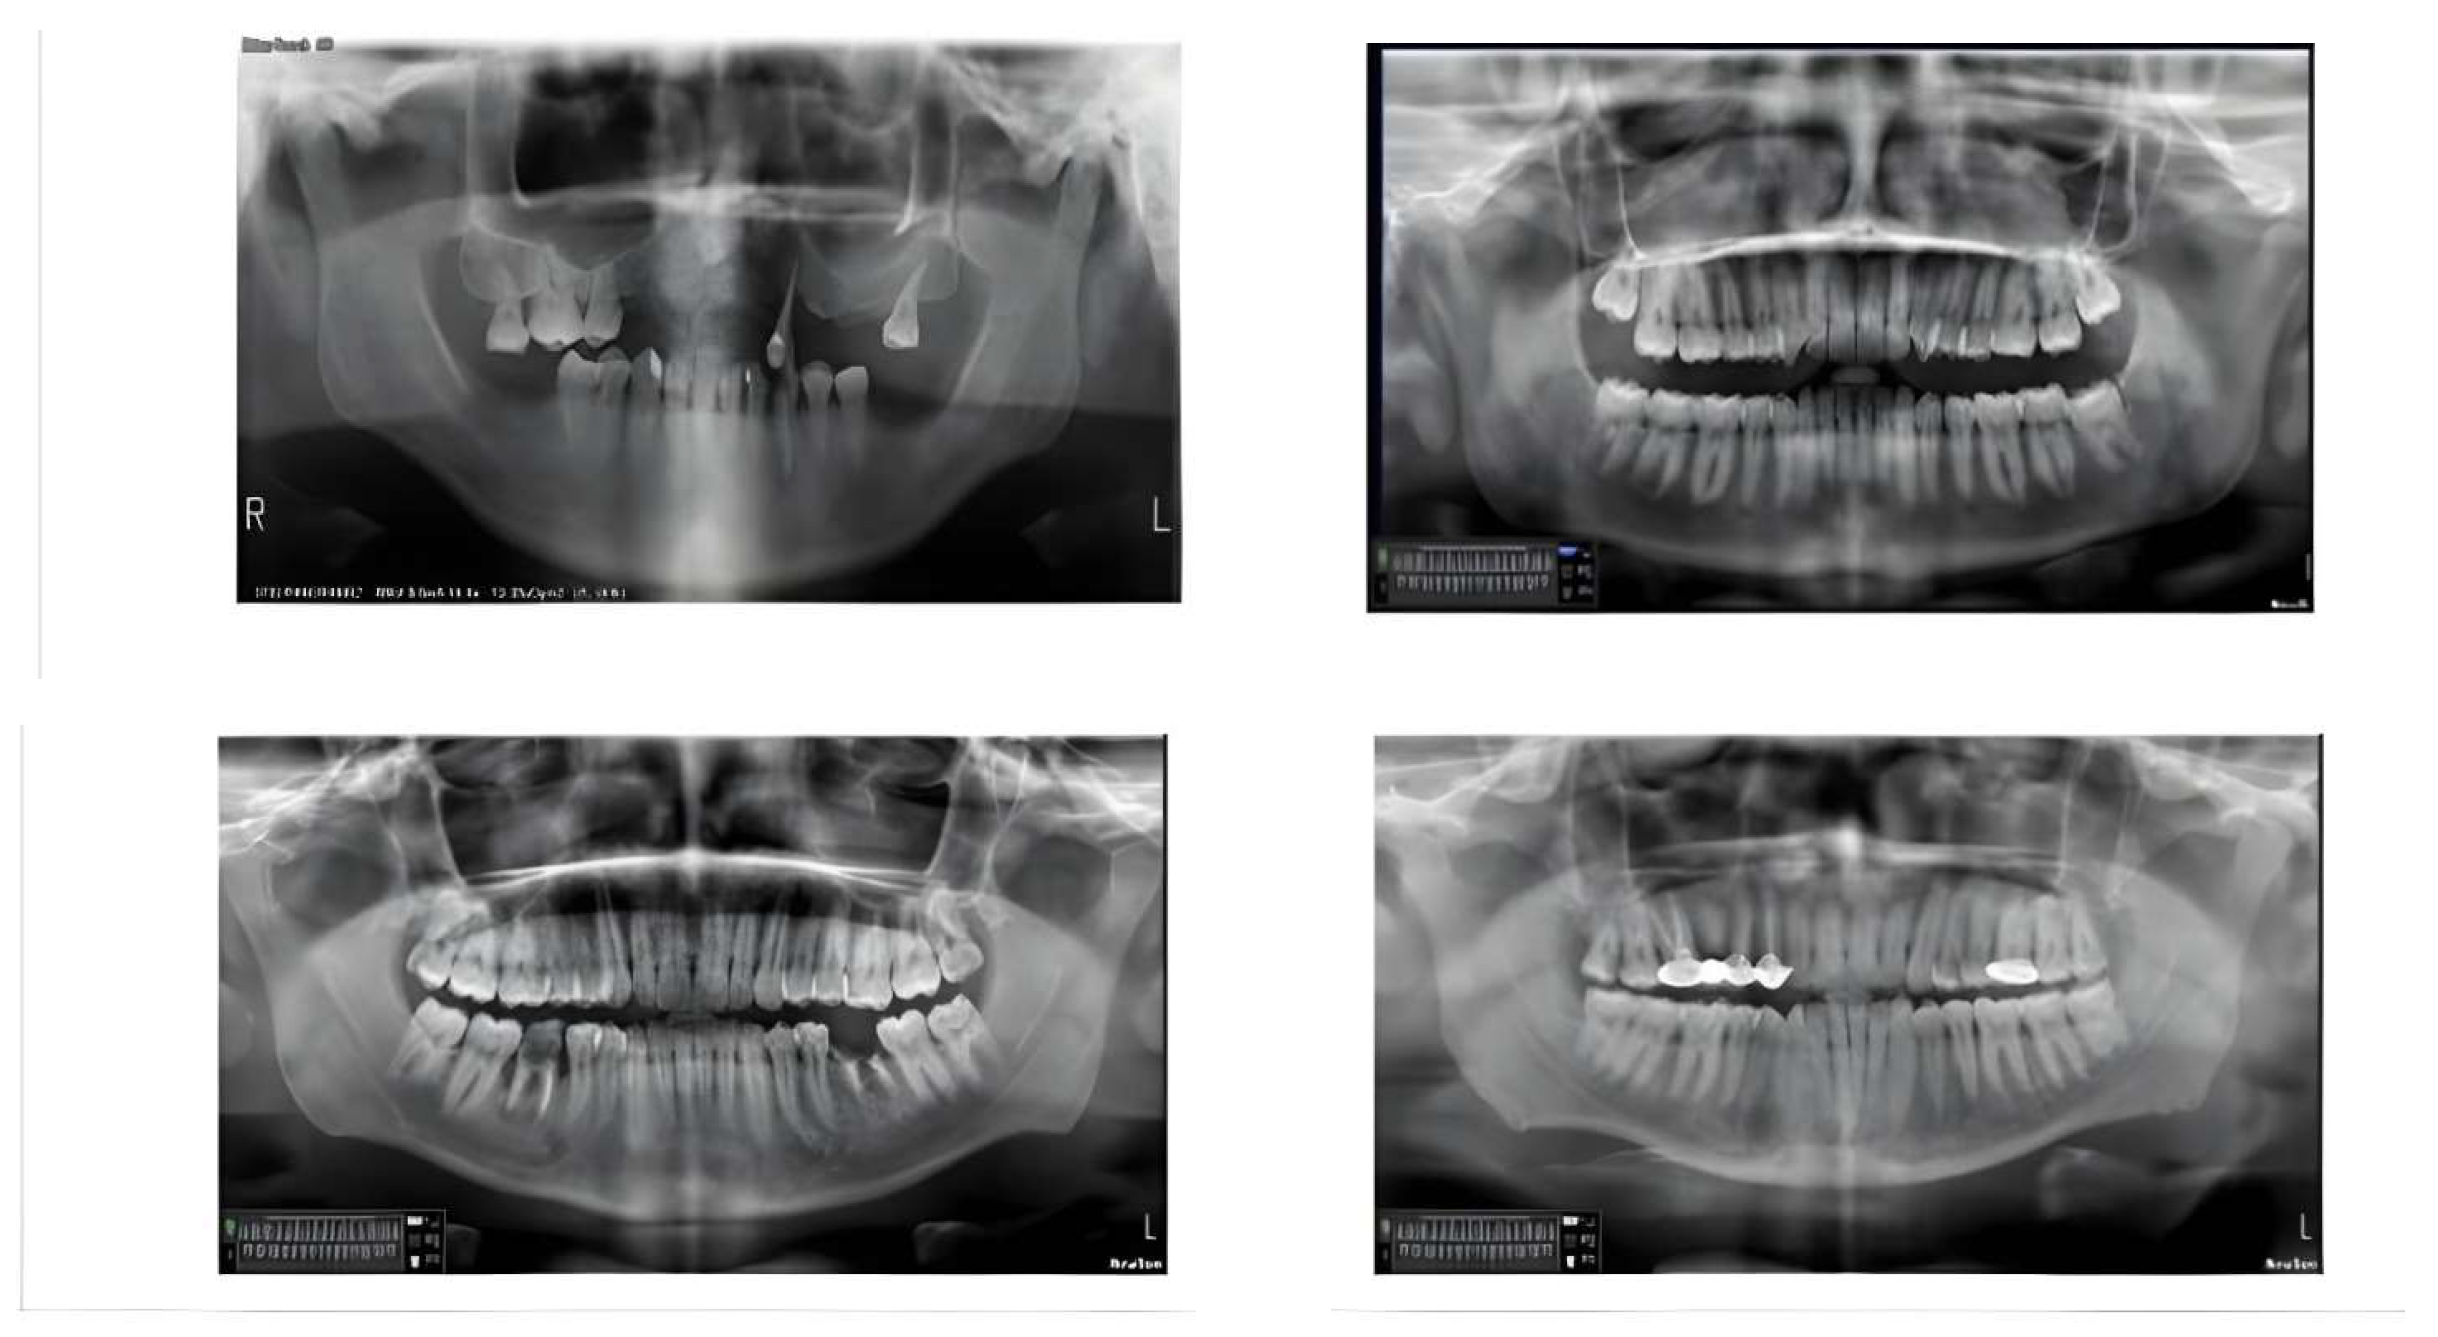

2.2. Dataset Collection and Preparation

2.2.1. Inclusion Criteria

- Image Quality: Radiographs with clear visualization of dental structures, including alveolar bone levels and periodontal ligament space.

- Diagnostic Relevance: Radiographs that provide sufficient detail for periodontal bone loss assessment.

- Patient Age: Radiographs from patients aged 18 years and above to ensure complete dentition development.

- Clinical History: Cases with documented periodontal diagnosis or relevant clinical history.

- Radiograph Type: Only digital panoramic radiographs were considered to ensure image quality and format consistency.

- Timeframe: Radiographs taken within the past three years to ensure data relevance to current clinical practices.

2.2.2. Exclusion Criteria

- Poor Image Quality: Radiographs with severe distortions, artifacts, or insufficient contrast that may hinder accurate diagnosis.

- Incomplete Dental Records: Cases lacking sufficient clinical history or periodontal diagnosis details.

- Primary Dentition: Radiographs showing primary or mixed dentition were excluded to maintain focus on adult periodontal conditions.

- Post-Surgical Radiographs: Images taken after surgical interventions that alter bone structure significantly.

- Non-Panoramic Images: Radiographs such as periapical, bitewing, or CBCT scans that do not meet the panoramic format requirement.

- Pathological Conditions: Cases with extensive bone pathology unrelated to periodontal disease (e.g., tumors and cysts) were excluded to avoid confounding factors.